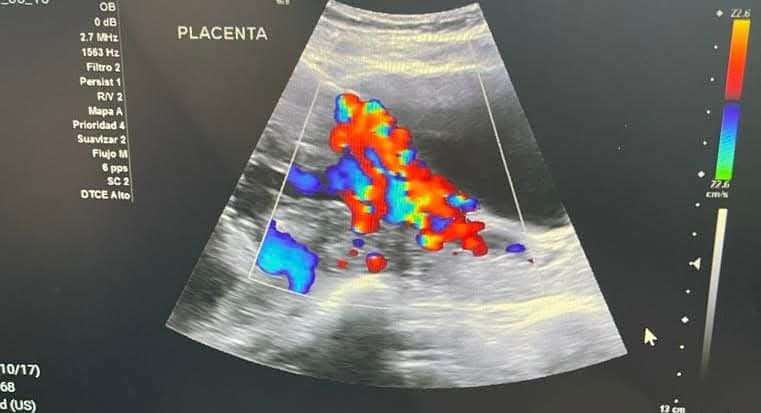

Chacón Lechuga indicó que la mayoría de los casos atendidos son por acretismos placentarios en sus tres niveles: acreta, percreta e increta, es decir, que la placenta está adherida de una manera anormal a la matriz, a otros órganos y a los vasos sanguíneos, lo que puede provocar una hemorragia severa.

Señaló que a nivel mundial, una de cada cuatro personas con esta patología fallece, pero que desde junio de 2018, en la ciudad de Chihuahua no se ha registrado una muerte materna directa por causas obstétricas propias del embarazo en el hospital.

Fátima Rodríguez, usuaria de la clínica, es una madre de tres infantes que a sus 22 años, en su último embarazo, presentó placenta percreta, y que fue atendida en el Hospital Central gracias al programa MediChihuahua.

En el nosocomio, la plantilla de especialistas estuvo al pendiente de su desarrollo, la cirugía y su recuperación, para lograr preservar tanto su vida como la de su bebé.